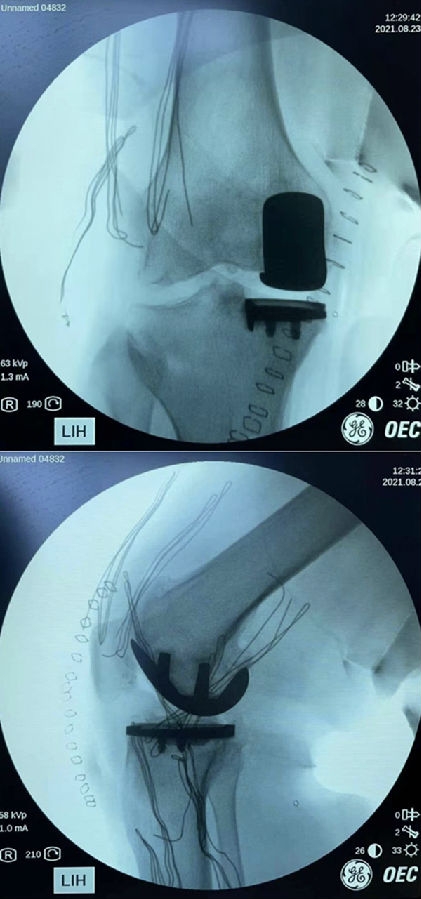

患者女,65岁,通过负重正侧位片,诊断:前内侧骨关节炎,符合单髁置换指征。术中发现外侧小片软骨剥脱。但是,术前屈曲二十度外翻应力位,外侧关节间隙完好,仍按计划行单髁置换术。

术后

本例患者术前内翻就比较重,术中恢复韧带原有张力后,仍刻意保持力线内翻,外侧间室保持2毫米减压松弛,从以往截骨经验来看,外侧这点软骨损伤,在关节内整体力学环境恢复到接近正常的情况下,对近期影响很小。远期生存率有待进一步观察。临床中对于这种膝内翻较重的患者,合并外侧软骨小剥脱,还是建议要综合力线、术前症状、年龄、身体状态等因素多方面考虑,对于体弱多病,高龄患者,为了减少创伤,仍倾向于单髁置换术。此时,力线控制就显得尤为重要,在恢复内副侧韧带张力的同时,要确保整体力线内翻,外侧处于减压状态,才能最大限度的降低外侧病变的影响。